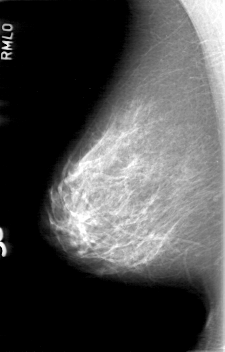

D_4058_1.RIGHT_CC

RIGHT_MLO LINES 5266 PIXELS_PER_LINE 3361 BITS_PER_PIXEL 12 RESOLUTION 43.5 NON_OVERLAY